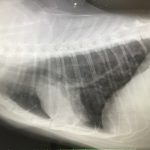

レントゲンを撮り診断の結果、軽度肺炎と診断されました。

そのときのレントゲン画像です。

黒く抜けているところが肺です。右側にすこしもやがかかっている箇所があり、そのに炎症が起こっているとのことです。

2週間抗生剤とステロイドを服用すると咳がなくなりました。

念のため1か月後レントゲン撮影。

1か月前と比べてもやが少なくなりました。